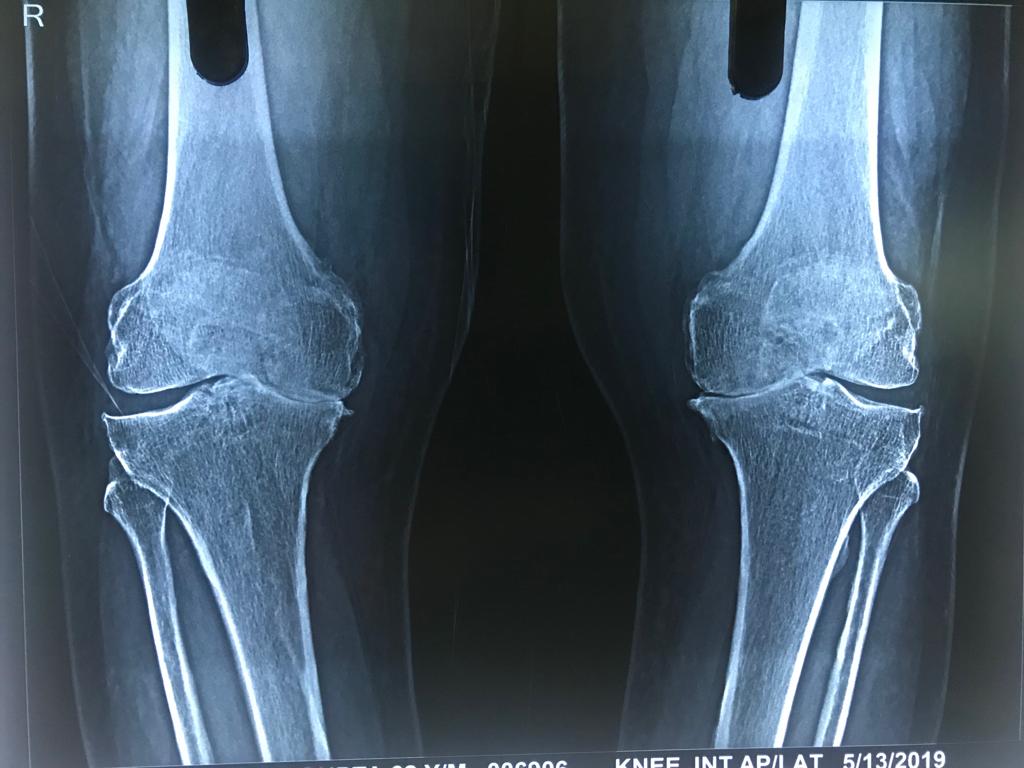

Case I: This is a case of bilateral total knee replacement